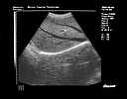

问题 图中肝脏图像最长的管道为?(?)

选项 A.肝右静脉 B.肝中静脉 C.门静脉右支 D.下腔静脉肝段 E.门脉左支

答案 A